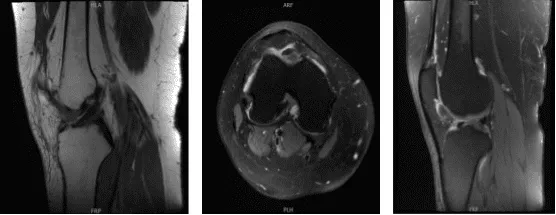

Which showed lateral tilt of the patella towards the trochlea along with advanced patellofemoral arthritis with mild medial compartment arthritis. Also, the MRI was done to confirm the findings.

MRI-3T Right knee non-contrast